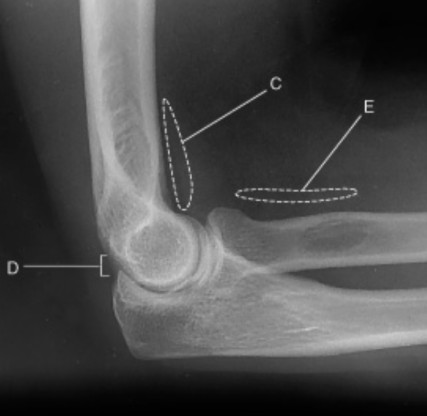

On this true lateral elbow projection, what does C represent?

anterior fat pad

On this true lateral elbow, describe the appearance of C

anterior fat pad is teardrop shape

On this true lateral elbow projection, what does D represent?

posterior fat pad

On this true lateral elbow projection, when does the posterior fat pad become visible?

only visible when there is pathology

On this true lateral elbow projection, what does E represent?

supinator fat stripe

On this true lateral elbow projection, which fat pad is only demonstrated when there is pathology?

On this true lateral elbow projection, when is E commonly used for? Hint: used to d______

may be used to diagnose radial head or neck fractures